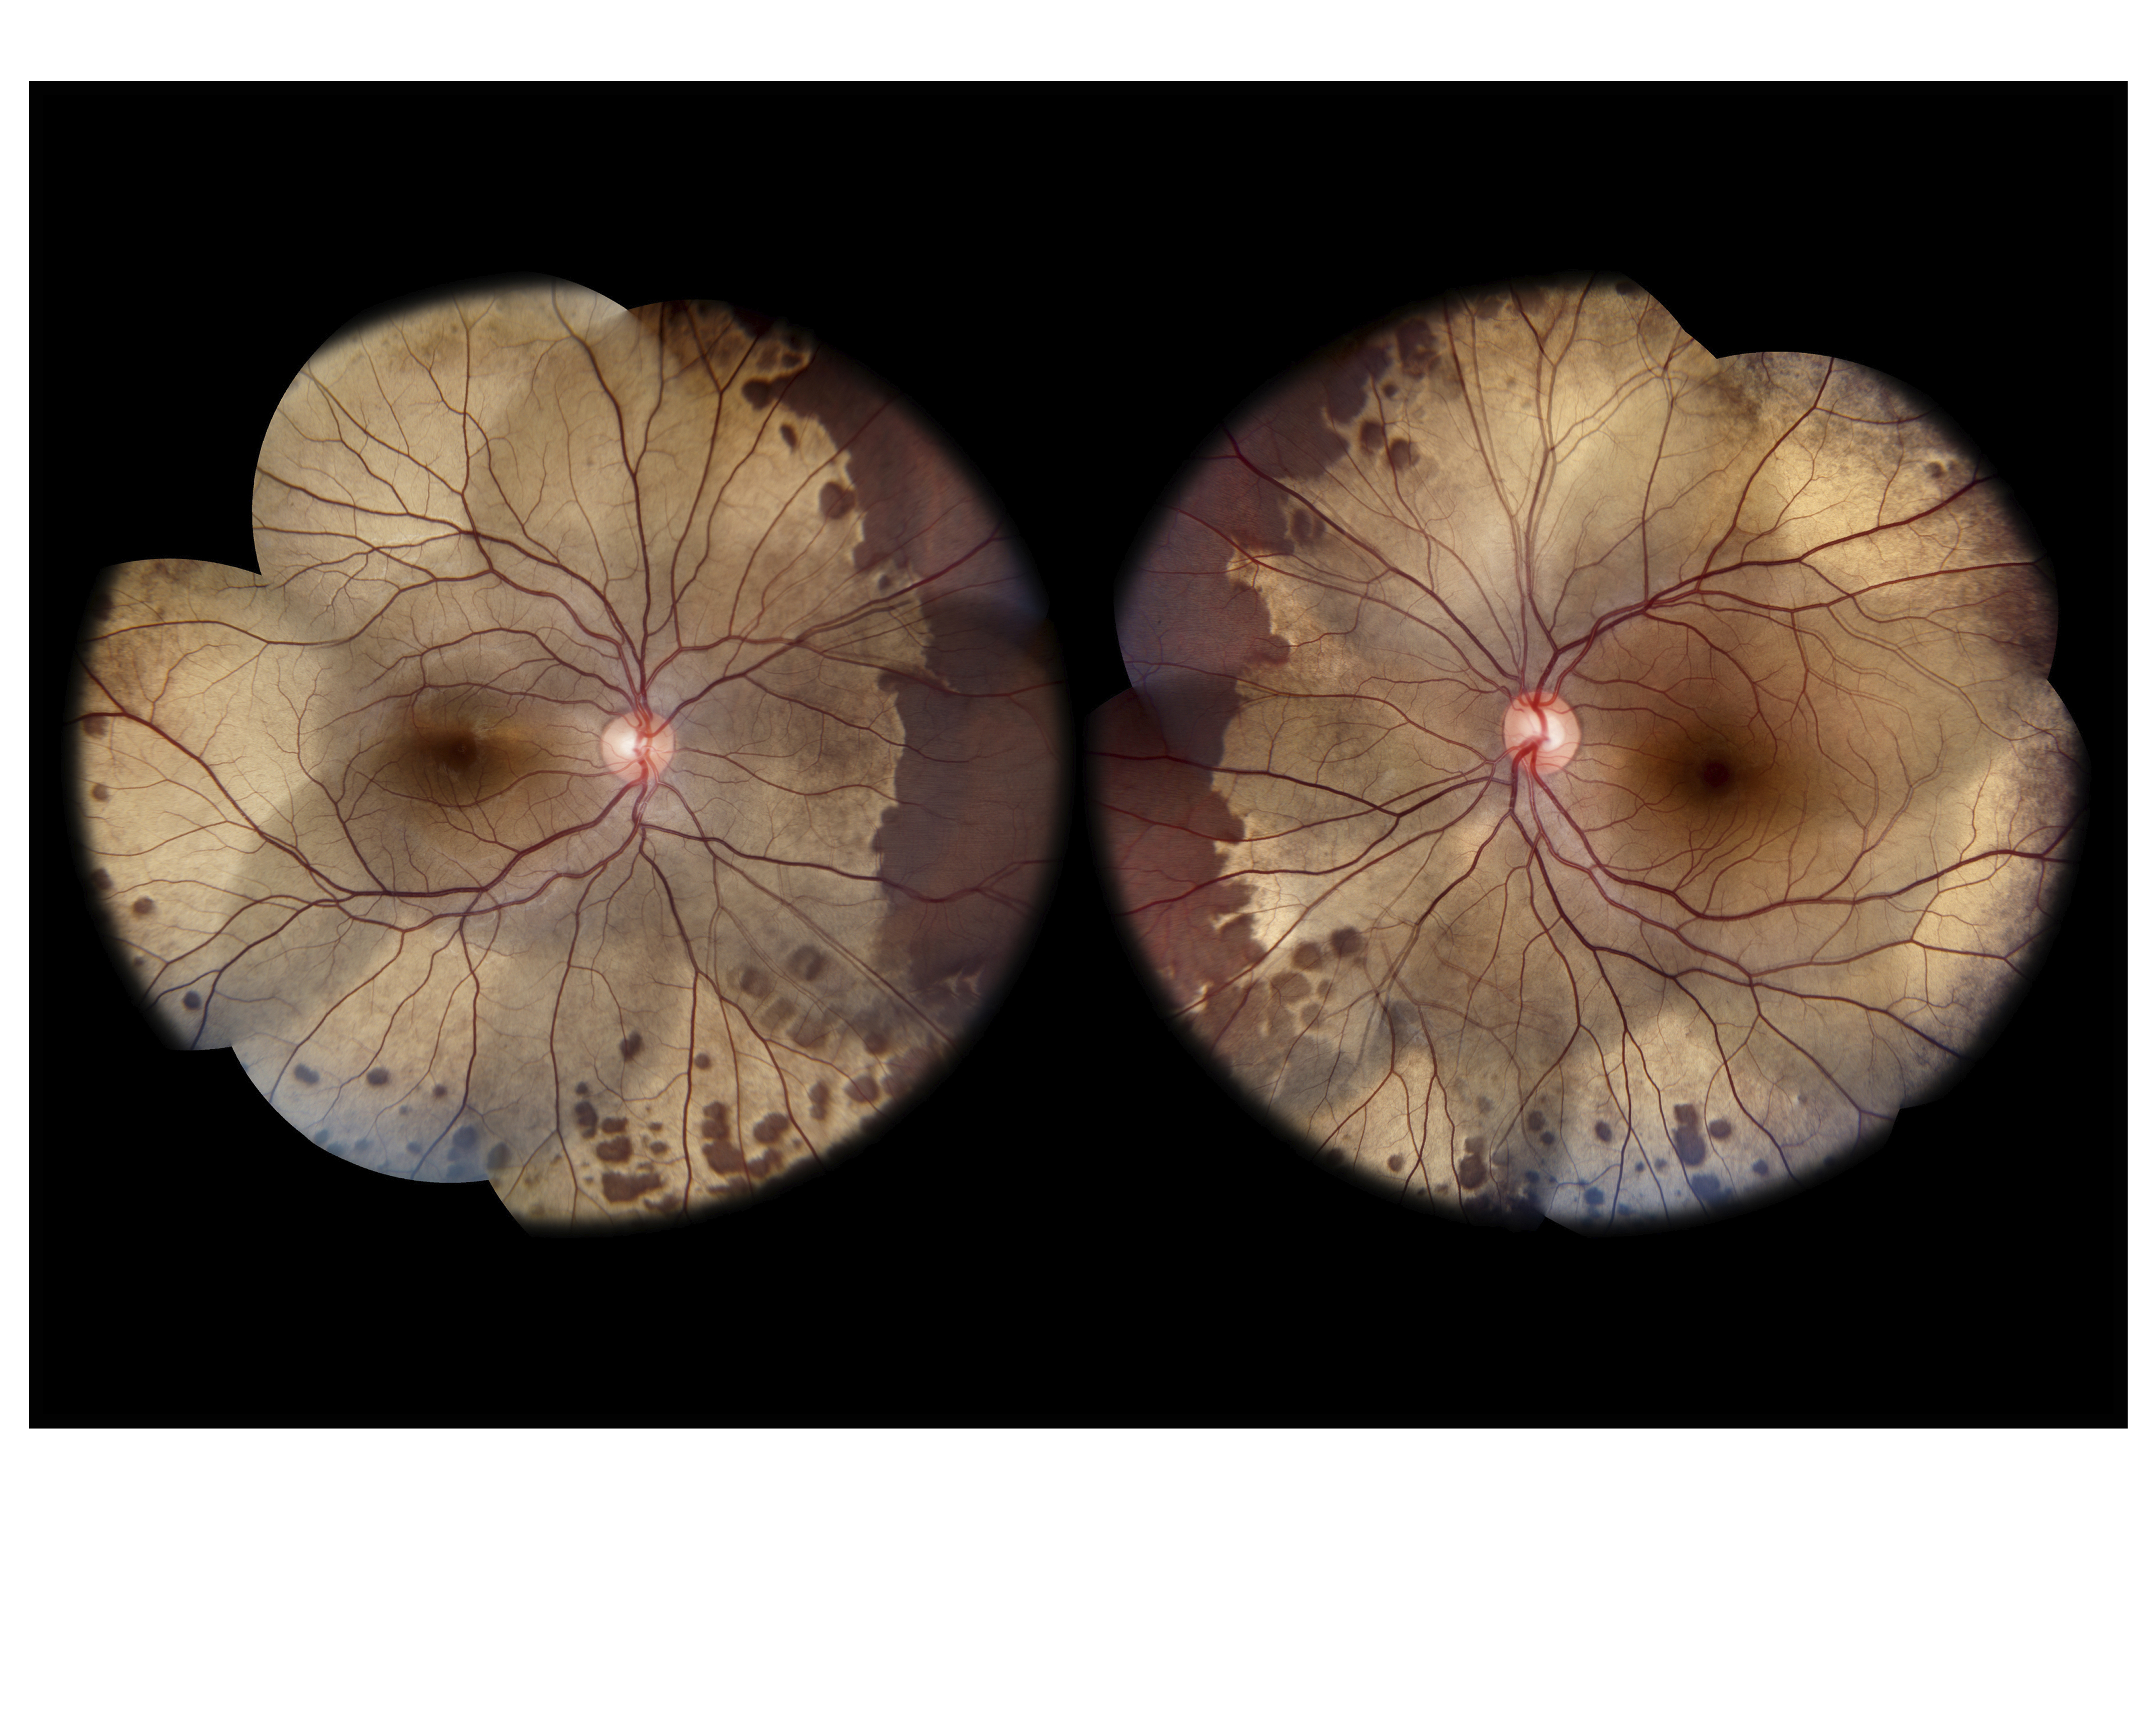

OGuchi Disease Presented by John Leo This photograph received First Place in the category "Composite" and was displayed in the 2024 OPS Exhibit. Filed Under Retina OPS Photo